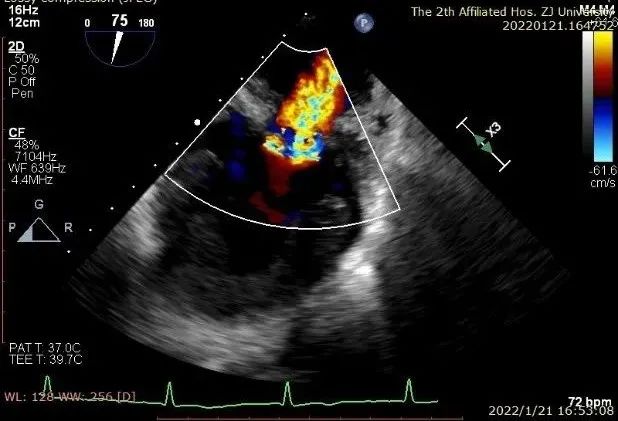

患者一术前二尖瓣反流重度4+